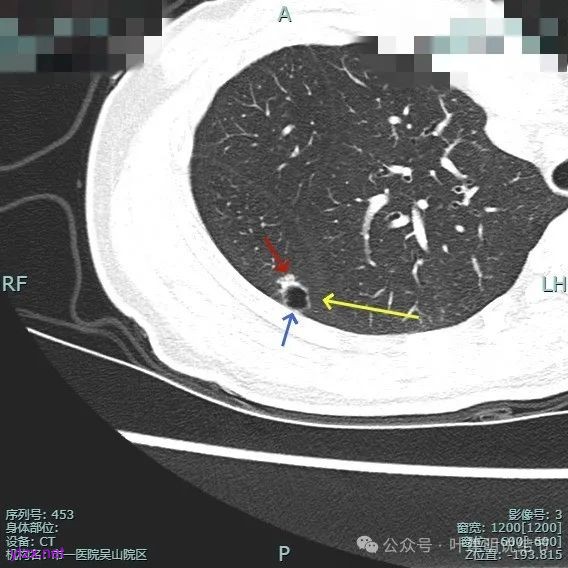

非薄层平扫上这个层面比较明显,似一囊腔,壁厚薄欠均匀。

薄层上看病灶贴着叶间裂与胸膜,此层囊壁薄,囊腔明显。

囊壁局部有增厚。

囊壁局部较厚,但囊壁内也是有小空泡的,病灶贴着胸膜。

病灶部分囊壁是混合磨玻璃成分的,整体轮廓较清。

边缘区也有偏实性成分,磨玻璃成分也还是明显的,有微小血管进入。

靶重建的影像上看,病灶的囊壁明显厚薄不均,有小血管进入,一侧的边似就是斜裂的样子。

囊壁有磨玻璃成分,边缘毛糙,有少许偏实性成分,仍有磨玻璃成分。

血管走向病灶,囊壁略不均。

此层见囊壁有较明显实性成分,血管进入明显。叶间裂侧平直。

混合密度,收缩力不明显,血管进入明显。

囊壁混合密度,整体轮廓清。

表面不平,血管进入,囊壁厚薄不均,紧贴叶间裂。

囊壁里面也有小空泡征。

混合密度但还是太致密,内壁毛糙不平。

病灶轮廓清楚,囊壁厚薄不均,贴着叶间裂与胸膜。

1、诊断问题:这是很典型的囊腔型肺癌,符合我自己之前提出的囊腔型肺癌三要素:(1)囊壁厚薄不均;(2)血管进入囊壁;(3)囊腔内壁不光滑(或再加止整体轮廓与边界较清)。而且由于囊壁实性成分明显,所以是有风险的,要及时干预处理。